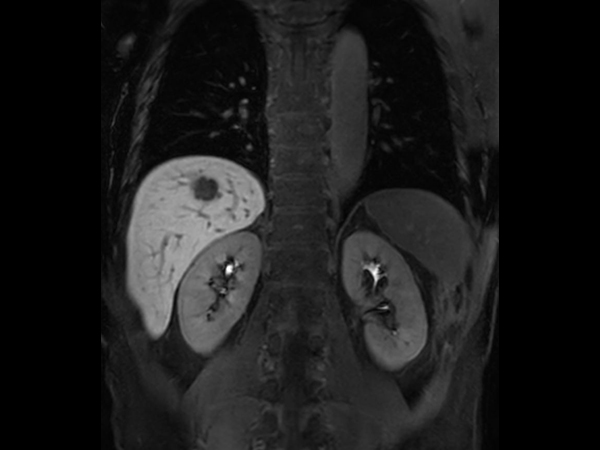

Liver metastasis – Free breathing

Patient with liver metastasis. ExamCard includes Compressed SENSE to shorten the breath hold time, VitalEye for touchless respiratory sensing, mDIXON Quant for non-invasive liver fat fraction quantification and 4D FreeBreathing to perform multi-phase contrast-enhanced MRI studies.

T2w SPAIR - Breath hold